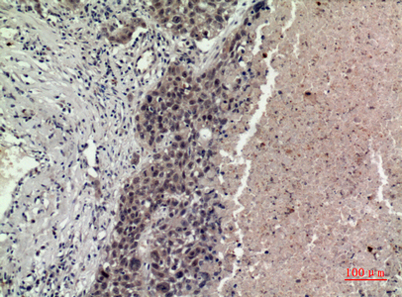

| Dilutions: | Western Blot: 1/500 - 1/2000. IHC-p: 1/100-1/300. ELISA: 1/20000. Not yet tested in other applications. |